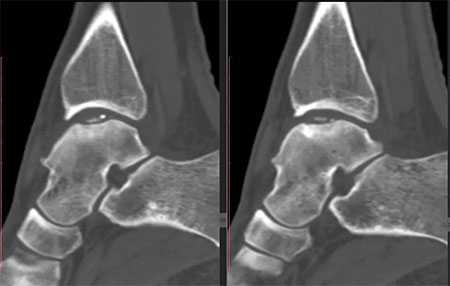

На КТ определяется остеохондральное повреждение таранной кости.

а. на рентгенограммах артроз голеностопного сустава, б. на КТ голеностопного сустава некроз таранной кости.